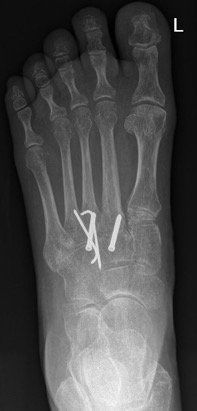

Surgery for midfoot arthritis ranges from simple to more complex procedures. Surgery may involve a “clean-up” of the joint by removing damaged cartilage and bone spurs, resection of a part of the joint, fusion (stiffening) of one or more joints. Medical imaging, such as x-rays and MRIs are usually obtained prior to surgery to determine the extent of the injury and to plan for the proposed surgery.

Rehabilitation varies according to the procedure performed. In some cases patients are allowed to weight bear immediately following surgery, but in other cases they are required to be non-weight bearing for a period of time.